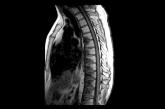

ArticleYour role in early diagnosis & Tx of metastatic bone diseaseAuthor:Humza Mian, BAPublish date: September 10, 2020This approach to the work-up and diagnosis will help you to ensure prompt treatment while maximizing your patient’s quality of life.Read More